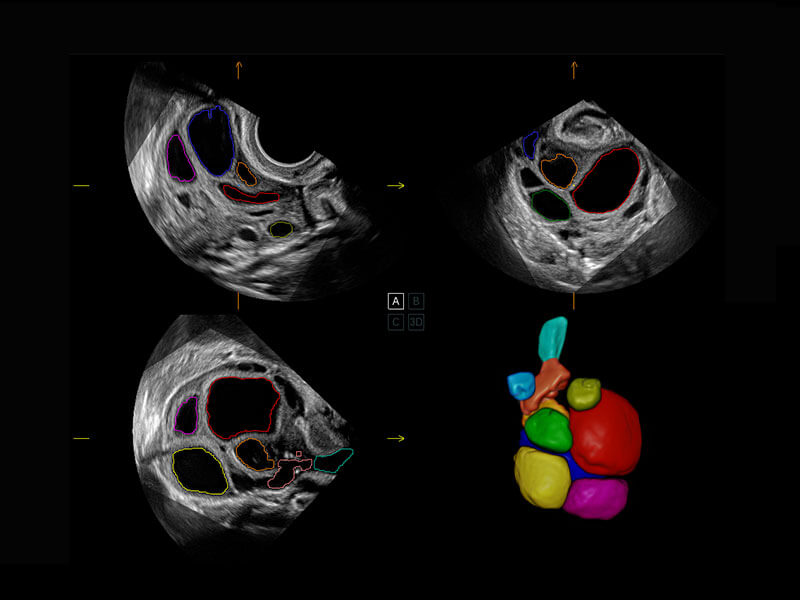

P60提供簡(jiǎn)單易學(xué)易用的高端診斷工具,為您中晚孕篩查提供快速清晰的解剖信息。

S-Fetus能夠助您在實(shí)時(shí)掃查過(guò)程中自動(dòng)識(shí)別標(biāo)準(zhǔn)切面、自動(dòng)測(cè)量并錄入報(bào)告。一個(gè)按鍵,即可快速、高效地獲取胎兒生理指標(biāo),簡(jiǎn)化您的產(chǎn)科檢查操作。

P60為盆底超聲檢查提供應(yīng)用方案,多種腔內(nèi)及腹部容積探頭提供從二維、三維到四維的優(yōu)異圖像品質(zhì),實(shí)時(shí)快速三維容積數(shù)據(jù)獲取,專(zhuān)業(yè)的測(cè)量工具包等人性化設(shè)計(jì),為超聲醫(yī)生診斷提供有力保障。

能夠簡(jiǎn)化盆底檢查的操作流程,可在二維模式及三維成像模式下實(shí)現(xiàn)一鍵自動(dòng)提取出標(biāo)準(zhǔn)切面、自動(dòng)識(shí)別當(dāng)前切面、自動(dòng)測(cè)量,提升盆底檢查的高效性,同時(shí)也能讓青年醫(yī)生快捷的獲得準(zhǔn)確的檢查結(jié)果。